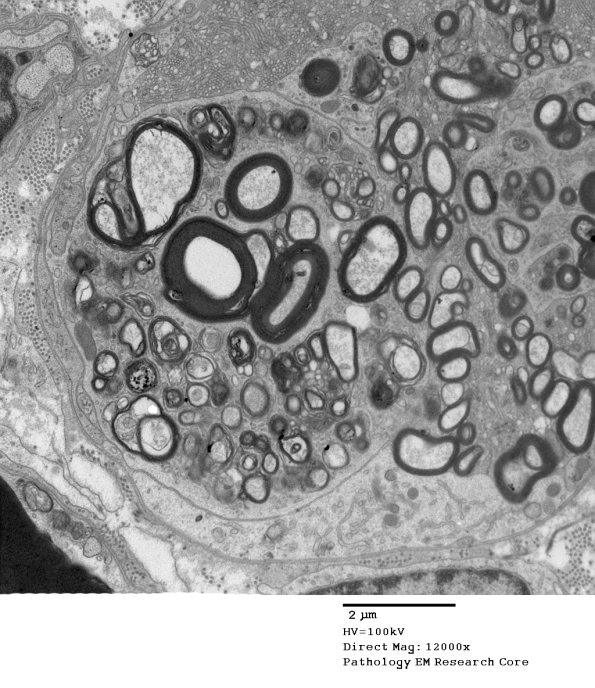

This collection of myelin debris appears discrete and surrounded by a unit membrane between it and other Schwann cell contents but still is maintained within the original Schwann cell basement membrane.